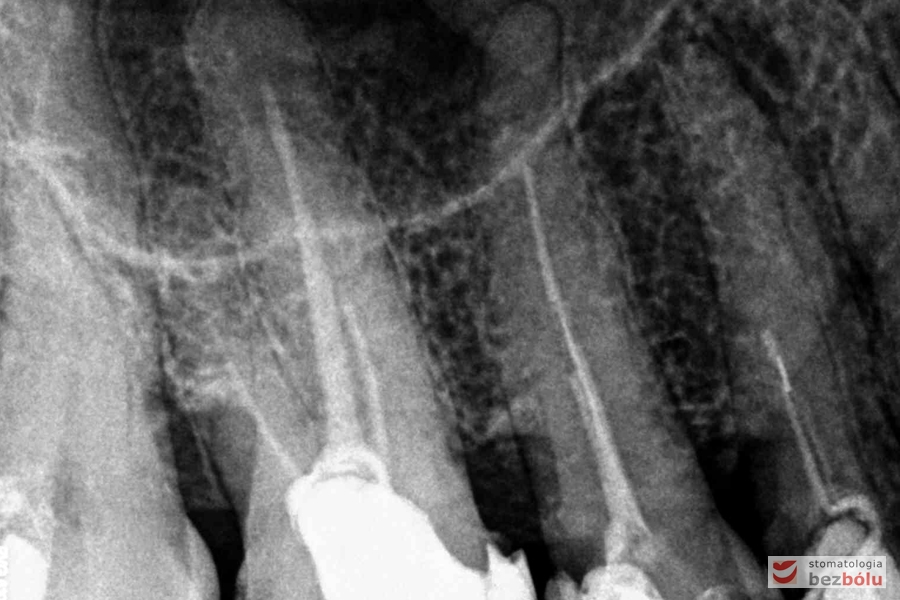

Radiowizjografia - szóstka, piątka, czwórka prawa w szczęce, wszystkie kanały niedopełnione

Radiowizjografia – szóstka, piątka, czwórka prawa w szczęce, wszystkie kanały niedopełnione